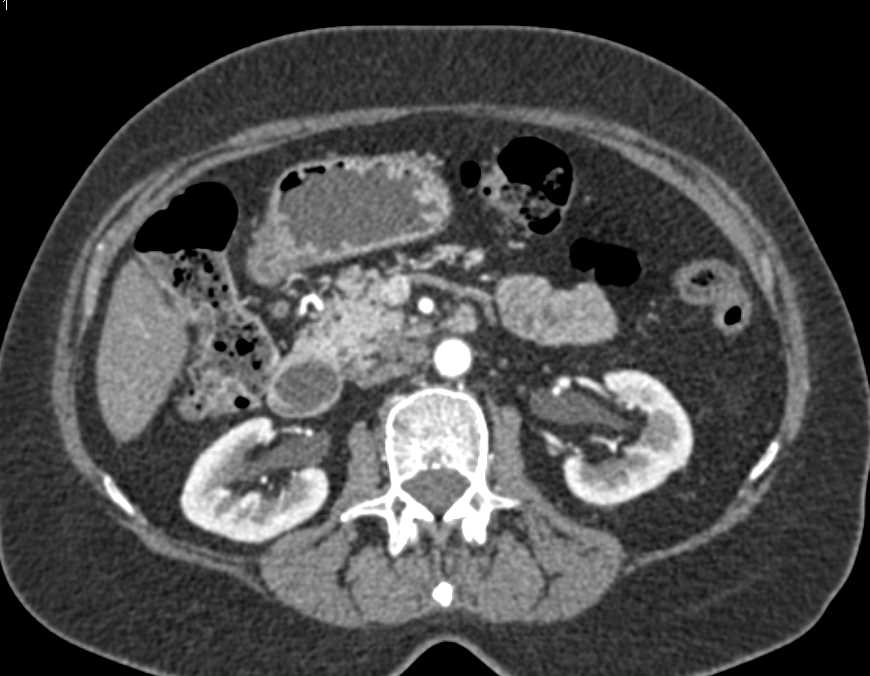

Duodenal Carcinoma with Obstruction